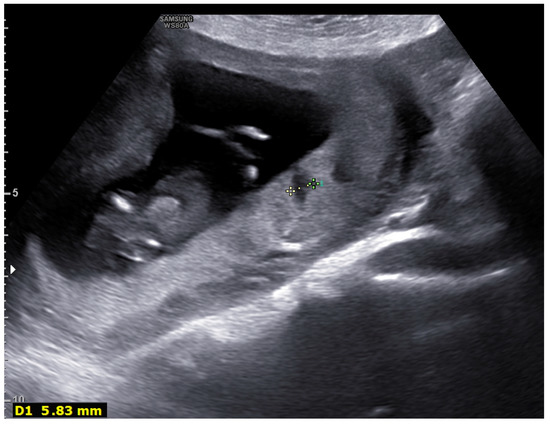

| 1 | Lakes > 30% |

| 1 | Fibrin deposits (thrombosis, calcifications) |

| Lakes > 30% | 7 (70%) | 6 (20%) |

| Fibrin deposits (thrombosis, calcifications) | 6 (60%) | 4 (13%) |